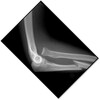

84

What pathology is present?

Radial head fracture